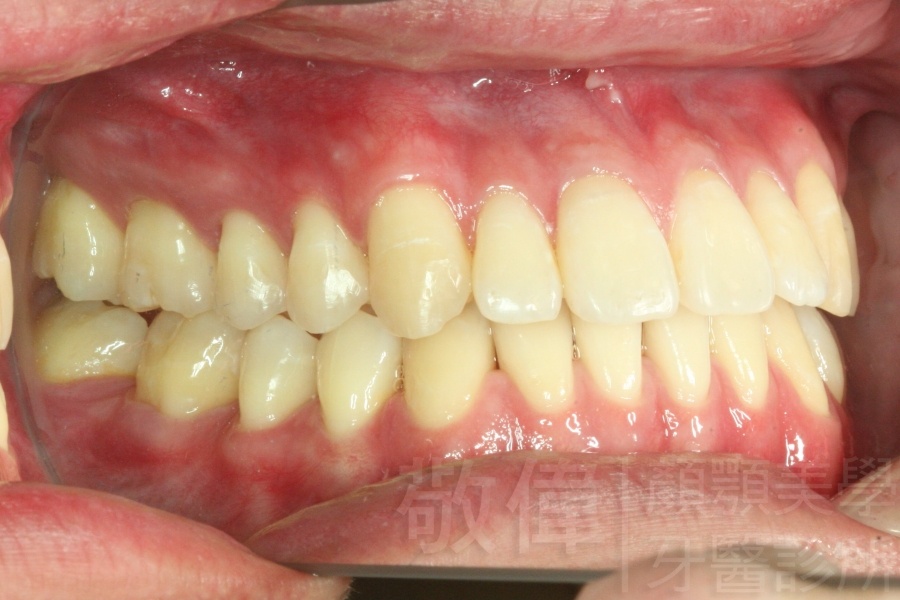

經由本院3D數影X光影像儀分析、與3D齒顎顏矯正技術,再配合口腔顎面正顎專科醫師施以正顎手術治療,雙方共同合作,使患者臉部外觀有很好的改善,大歪變小歪,產生了天南地北的大改變,她的人生也整個變得不一樣。

因為矯正與正顎手術的配合,使「戽斗妹」變成了「陽光正妹」,完全的改變了她的人生,在面對各種場合、與人交際都散發出自信微笑。所以,奉勸家長,如果小朋友有臉顎畸型的問題,應該考慮配合做這種簡單、安全、有效的正顎手術。

「3D齒顎顏矯正」,不止矯正您的牙齒,也會改變您的人生。「治療前」和「治療後」出社會的人生際遇一定會截然不同。